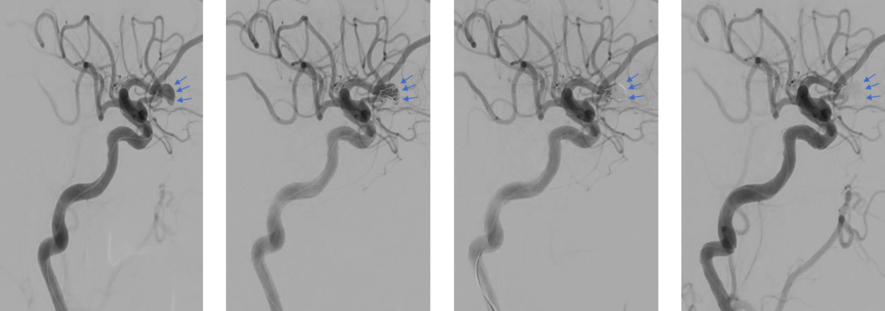

Die mit blauen Pfeilen markierte Aussackung (Aneurysma) der vorderen Hirnarterie kann mittelst einem kleinen Katheter mit Platinspiralen (Coils) vollständig aufgefüllt werden. Eine drohende Einblutung bei Einriss der Aneurysmawand und daraus folgendschwere Beeinträchtigungen können so verhindert werden.